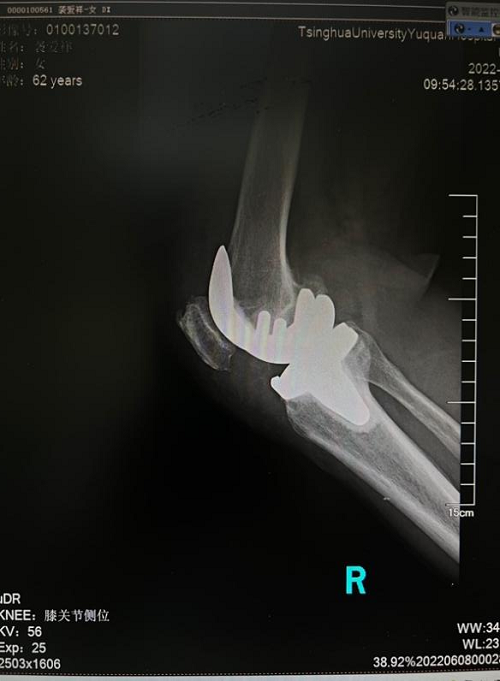

袭奶奶一听说人工关节大幅降价后,第一时间就找到骨科贾育松主任,接受了人工全膝关节置换手术。手术效果很好,恢复很快,第二天就在助行器的辅助下站立活动。出院两周后来门诊复查时,走路已完全不需要任何辅助,她表示对治疗效果非常满意,还说赶上了国家的好政策,既治好了病,也节省了治疗费用。